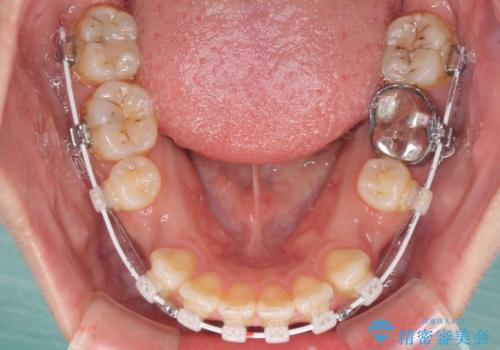

- 矯正装置

- 審美装置

- 唇の閉じにくさを気にして来院された患者様です。

上下左右第一小臼歯4本を抜歯し、ワイヤー装置にて口元を引っ込めるよう矯正治療を行うこととしました。